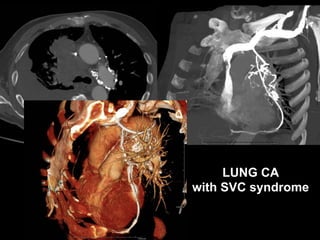

LUNG CA

with SVC syndrome